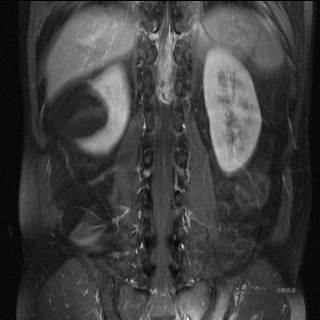

MR

T2

T2压脂